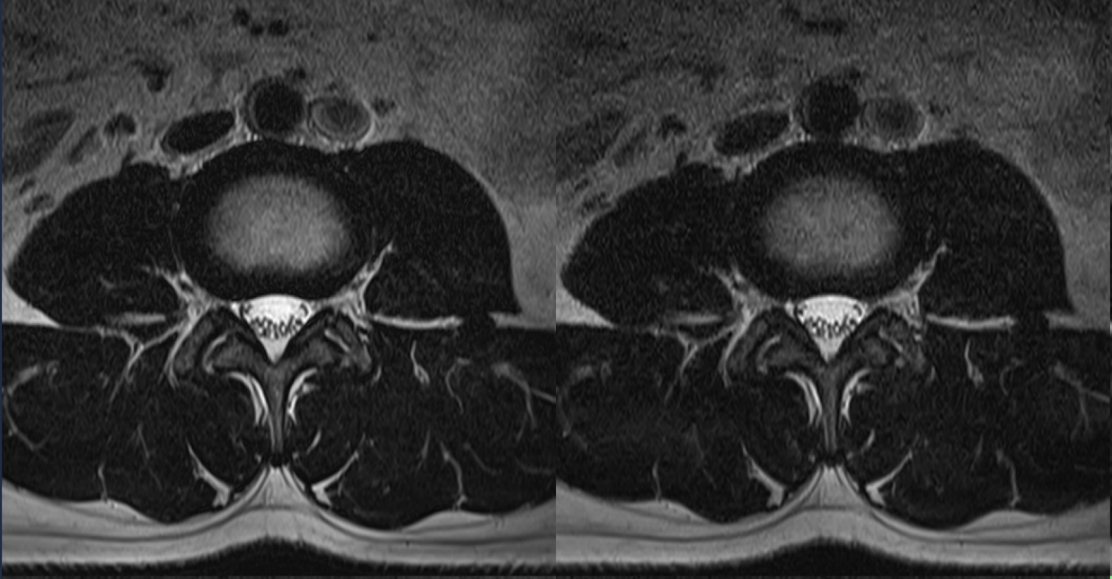

без Compressed Speeder

с помощью Compressed Speeder

Время сканирования 2:48

Время сканирования 1:24